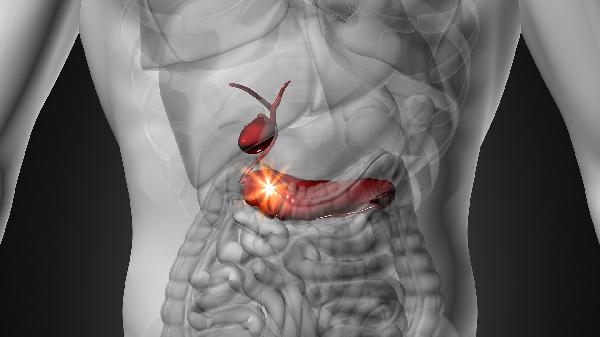

腹部彩超可以检查什么

腹部彩超可以检查肝胆胰脾肾等脏器结构异常、占位性病变及血流情况。主要有肝胆结石、脂肪肝、胆囊息肉、肾囊肿、腹主动脉瘤等情况。1、肝胆结石彩超能清晰显示胆囊和肝内......